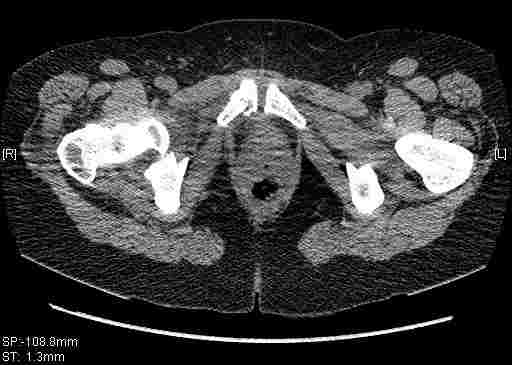

Женщина,58 лет, после ДТП 6 суток. Первично повреждение расценено как переломы ветвей лонной кости. После подтверждения повреждения вертлужной впадины,как чаще всего случается, вопрос встал о тактике. БОльшинство за консерватиное лечение.К сожалению кт у нас "во время" сломался. Прилагаю стандартные снимки вертлужки. У меня следующие вопросы к коллегам:1. Правильно ли рассценивать это повреждение как Т-образный перелом вертлужнй впадины?2. Можно ли добиться анатомической репозиции поверхности вертлужной впадины скелетным вытяжением в данном случае, если нет, что будет этому препятствовать?3. Если смещение останется таким как сейчас, через какое время появится необходимость эндопротезирования (по вашему опыту)?Спасибо.

Удалось сегодня вывести пациентку в соседнюю больницу, где есть кт. Срезы сделаны только горизонтальные.

Следом 3d

Приветствую,Антон.Рункова рядом нет,но после полученных данных КТ,обсуждали совместно.Итог обсуждения-развернутый ответ дать не получится,т.к.срезы выбраны не информативные.Если ориентироваться на данные 3D,то ,ИМХО,можно лечить на вытяжении.